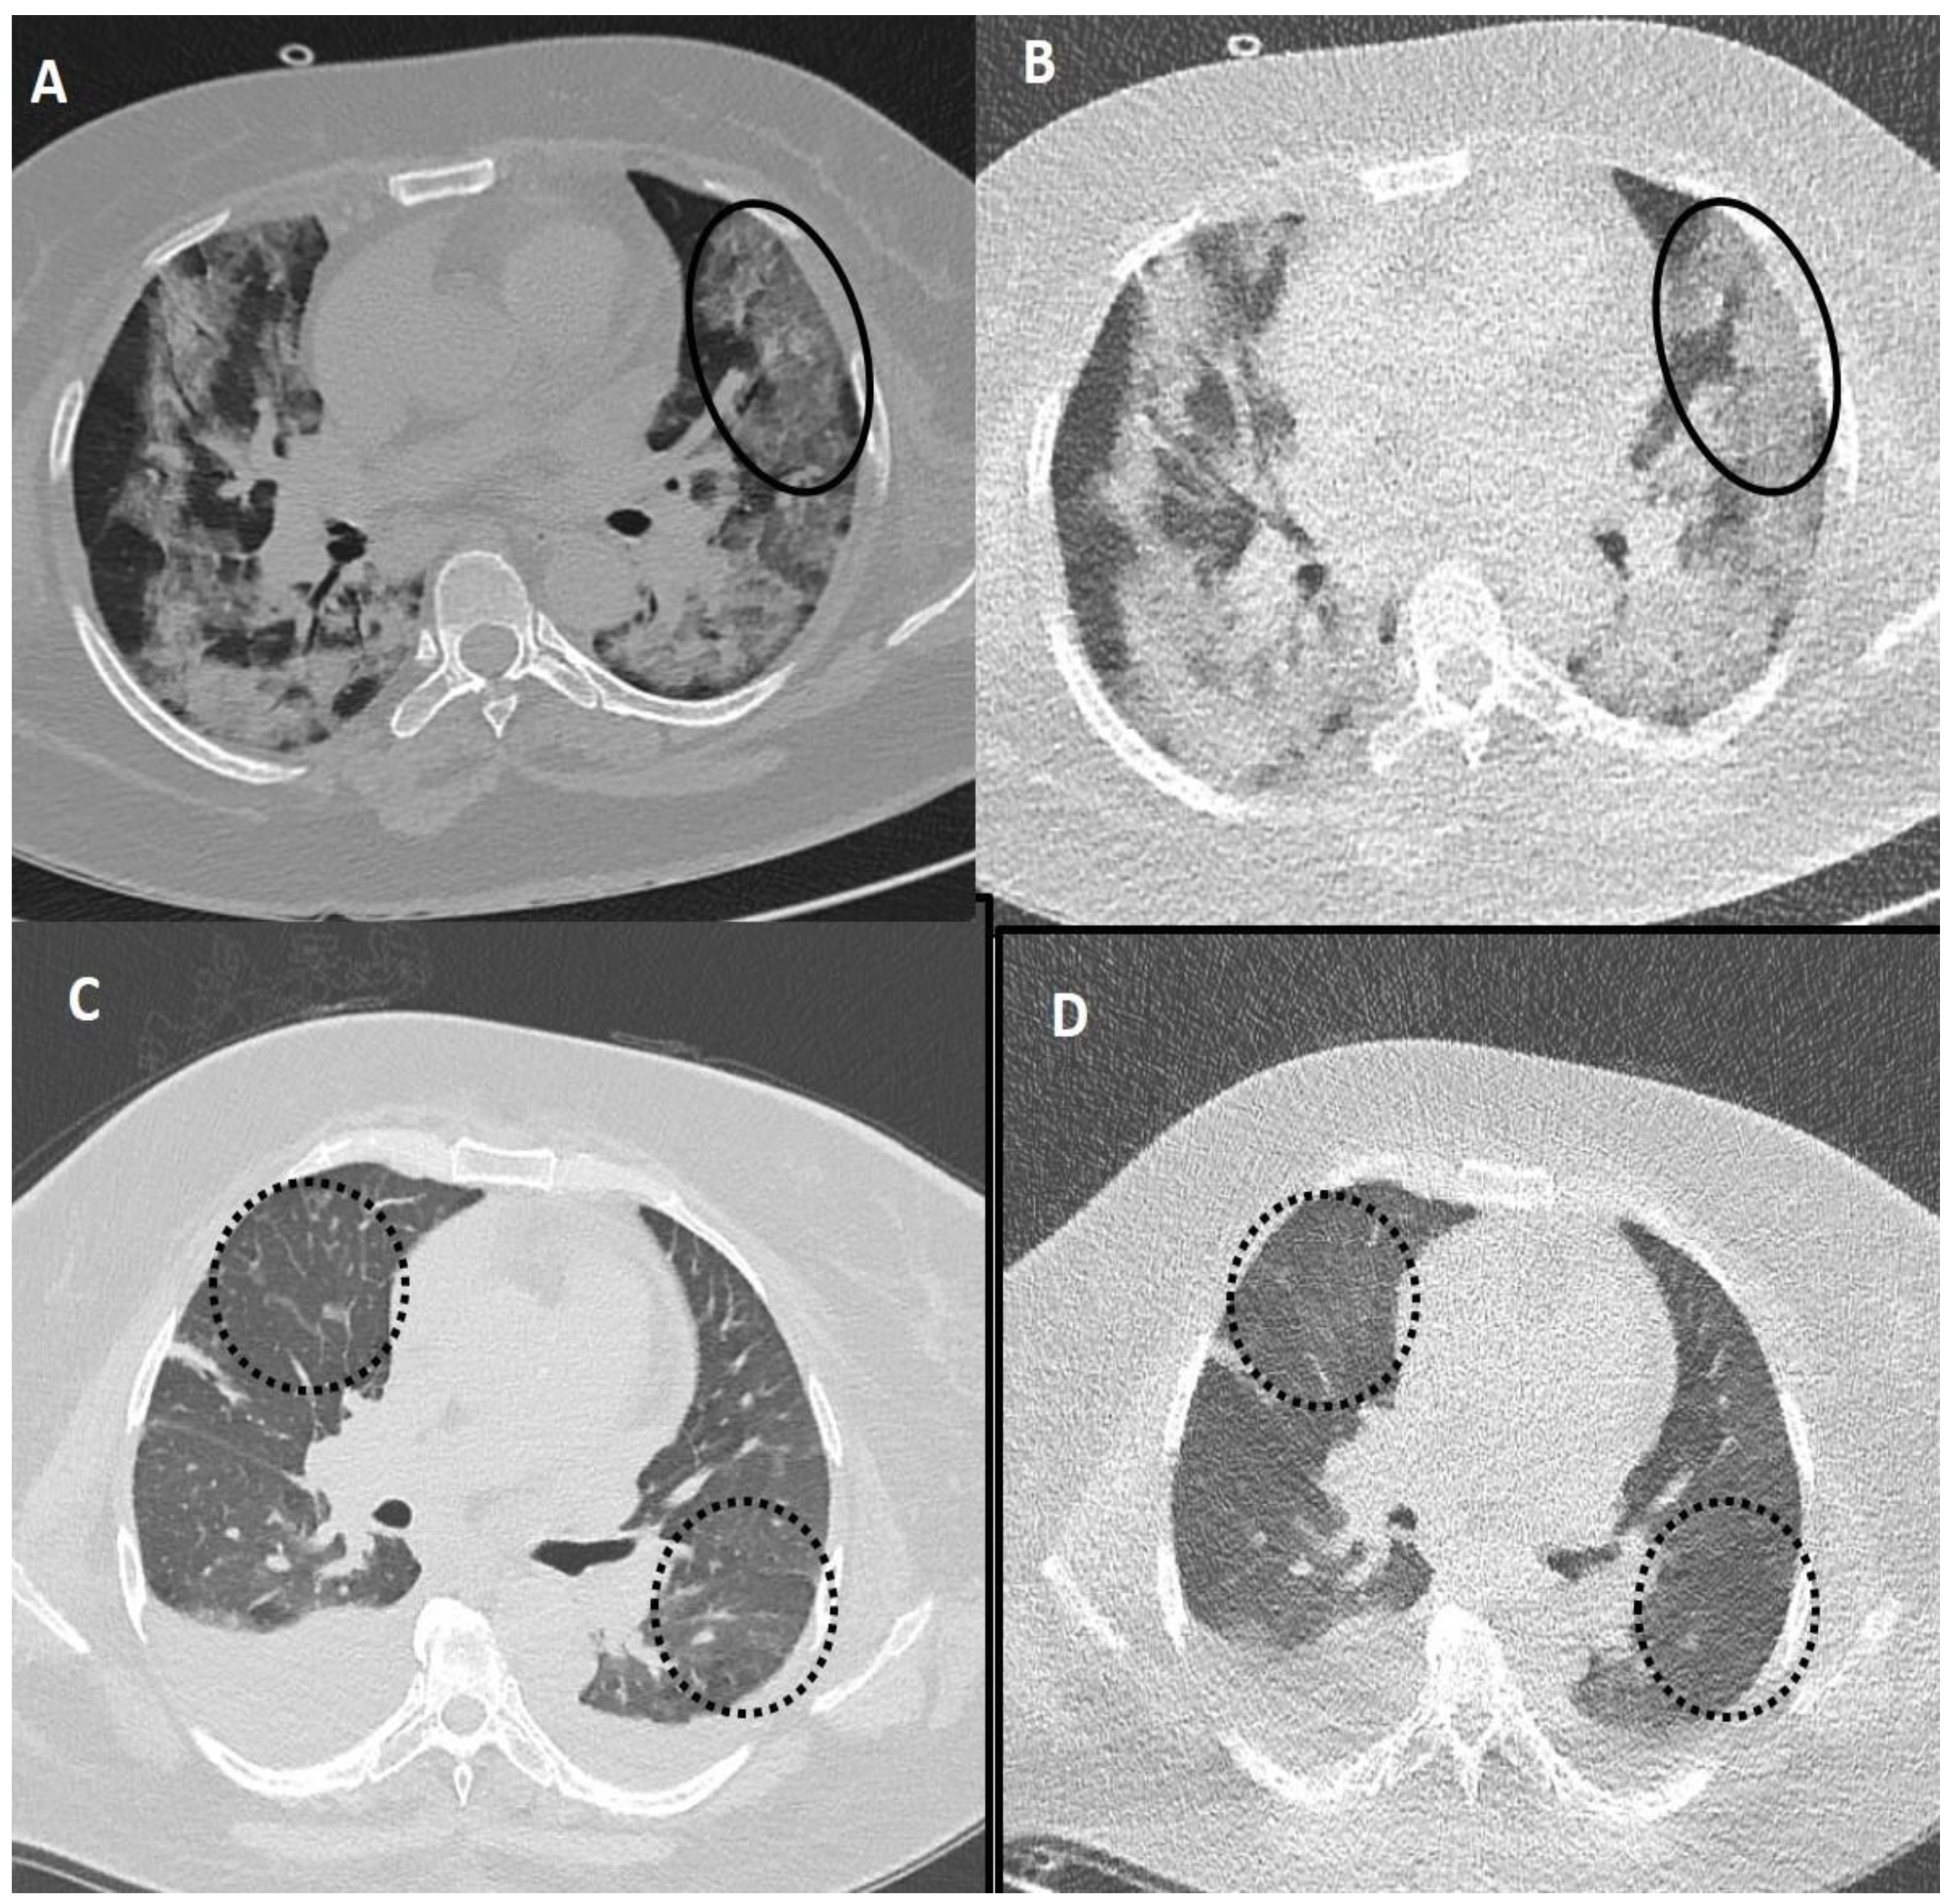

Figure 4.

Comparison of standard-dose CT (SDCT) chest and ultra-low dose CT (ULDCT) chest in two different COVID-19 patients: (A,B) A 51-years old male with SDCT (A) and corresponding ULDCT (B) images showing interlobular septal thickening/reticulation (black circles) and parenchymal bands (black arrows), with interspersed areas of GGOs in both lungs (dotted white arrows). (C,D) A 45-years old male patient with SDCT chest (C) and corresponding ULDCT chest (D) showing areas of GGOs with interlobular septal thickening giving a crazy-paving pattern (dotted circles). The CT severity score calculated on SDCT and ULDCT was found to be similar in both patients, while the effective radiation dose for SDCT was 4.63 mSv and 4.81 mSv, and for ULDCT was 0.26 mSv and 0.28 mSv, respectively.

Figure 5.

Fallacies of ultra-low dose CT (ULDCT) chest in two different COVID-19 patients: (A,B) A 53-years old female patient with SDCT (A) showing areas of GGOs in the left lung (black circle) and in the corresponding ULDCT (B) these areas of GGO’s were misinterpreted as consolidation (black circle). (C,D) SDCT images in another patient (C) showing subtle interlobular septal thickening in bilateral lungs (dotted circles) that was missed on the corresponding ULDCT (D) images (dotted circles). CT severity score calculated on SDCT and ULDCT, however, was similar in both patients.